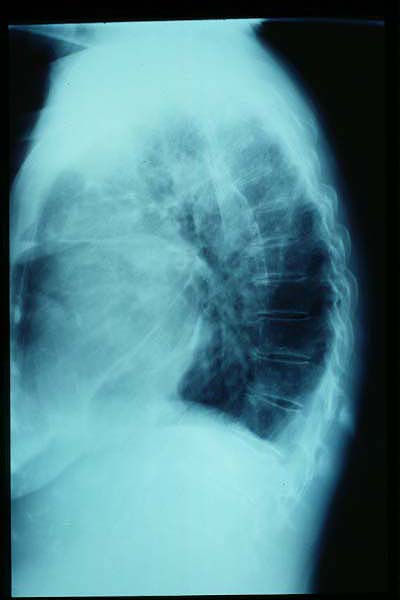

TBC pulmonar antigua